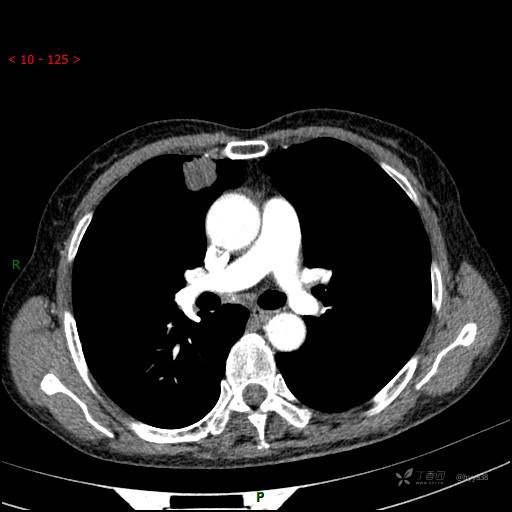

静脉期